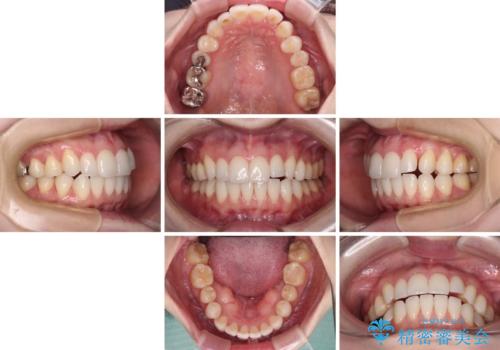

- 前歯のデコボコや八重歯の様になっていることを気にして来院された患者様です。

犬歯捻れて前方に飛び出しており、下顎前歯もそれに沿うようにデコボコとなっていました。

IPR(歯と歯の間を削る処置)によりスペースを獲得して上下顎前歯のデコボコを改善し、前歯が前方に突出しないように設定した上で、インビザラインにて矯正治療を行うこととしました。

途中体調を崩され、長い期間矯正治療を休むことになったため4年半ほどの治療期間がかかりました。